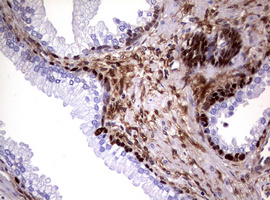

IHC analysis of GSTP1 using anti-GSTP1 antibody (BA0491).

GSTP1 was detected in a paraffin-embedded section of human ovarian cancer tissue. Biotinylated goat anti-rabbit IgG was used as secondary antibody. The tissue section was incubated with rabbit anti-GSTP1 Antibody (BA0491) at a dilution of 1:200 and developed using Strepavidin-Biotin-Complex (SABC) (Catalog # SA1022) with DAB (Catalog # AR1027) as the chromogen.